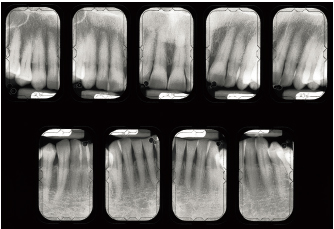

Fig 1-2a Aggressive periodontitis in a 50-year-old man. There is significant functional impairment; all teeth are mobile.

Fig 1-2b Destruction and attachment losses exceed 9 mm.

Fig 1-3a In this 40-year-old patient, periodontitis is moderate.

Fig 1-3b Destruction and attachment losses are evenly distributed throughout the dentition and are less than 30%.